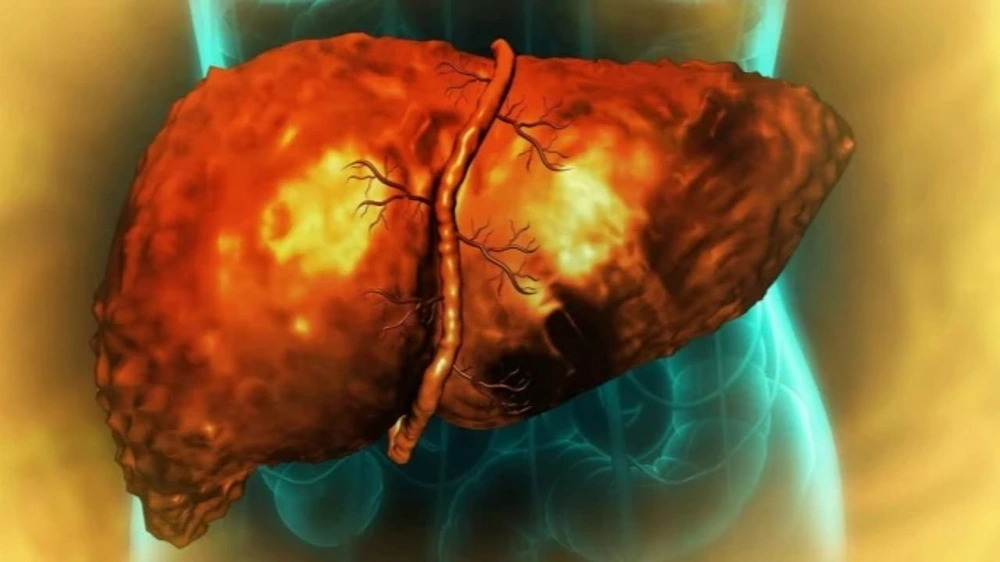

دراسة: الأنظمة الغذائية الغنية بالدهون قد تغير خلايا الكبد وتزيد خطر السرطان

حذر باحثون من آثار صحية خطيرة قد تنتج عن اتباع نظام غذائي غني بالدهون لفترات طويلة، مؤكدين أن الخطر لا يرتبط بكمية الدهون في الوجبة الواحدة، بل بمدة تعرض الكبد لهذا النوع من الغذاء.

وأوضحت الدراسة التي أجريت في معهد ماساتشوستس للتكنولوجيا، أن خلايا الكبد تدخل في حالة دفاعية عند تعرضها المستمر للدهون، وهو ما يجعلها أكثر عرضة للتغيرات التي قد تقود إلى الإصابة بالسرطان.

وأشار الباحثون إلى أن هذا التكيف طويل الأمد يغير من طبيعة عمل الخلايا ووظائفها الأساسية.

وبحسب ما نقلته شبكة "فوكس نيوز"، فإن الاستمرار على نظام غذائي غني بالدهون قد يدفع خلايا الكبد إلى العودة لحالة بدائية تساعدها على تحمل الضغط الغذائي، لكنها في الوقت ذاته تزيد من احتمالية تكوّن الأورام.

وبينت الدراسة أن الكبد، عند معالجته كميات كبيرة من الدهون بشكل متكرر، يتوقف تدريجيًا عن أداء مهامه الطبيعية مثل تكسير العناصر الغذائية وتنقية السموم، ويتحول إلى نمط بقاء يربطه العلماء بارتفاع خطر الإصابة بالسرطان.

وقال أليكس شاليك، أحد أبرز الباحثين المشاركين في الدراسة ومدير معهد الهندسة الطبية والعلوم في معهد ماساتشوستس للتكنولوجيا، أن الخلايا عندما تتعرض لضغط مستمر مثل الأنظمة الغذائية الغنية بالدهون، تلجأ إلى آليات للبقاء، لكنها تدفع ثمنًا صحيًا يتمثل في زيادة قابليتها للإصابة بالأورام.